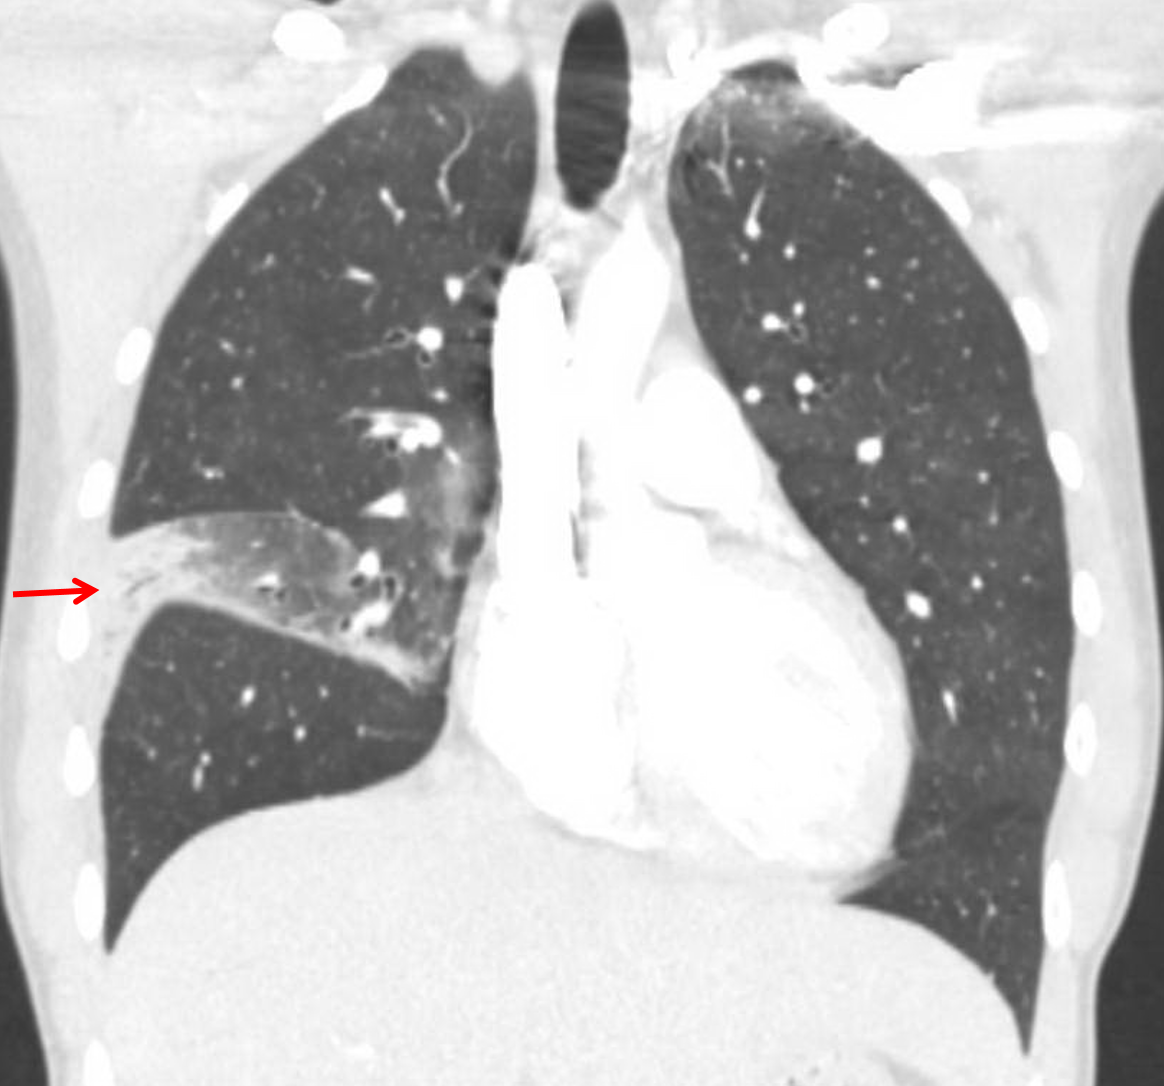

Age: 25

Sex: Male

Indication: Right-sided chest pain, cough

Sample ReportRight middle lobe pneumonia. Additional scattered groundglass opacities in the right lower lobe and lingula are likely also infectious in etiology.

Small right pleural effusion.